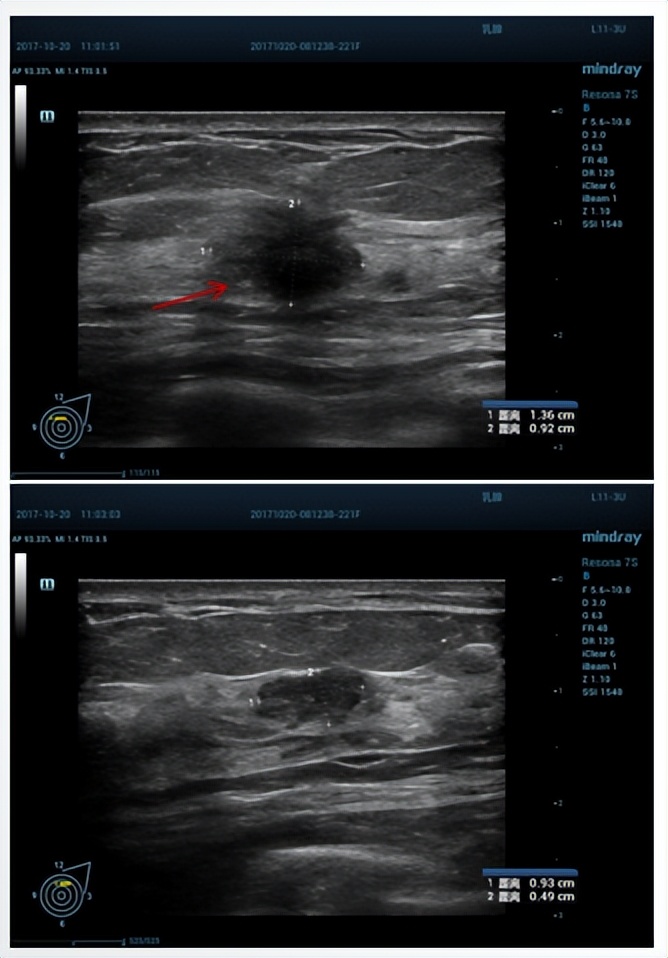

现病史:患者2周前无明显诱因发现左乳肿块,无外伤史,无疼痛不适,无乳头溢液,无皮肤红肿破溃,我院B超提示“左乳多发结节,较大结节BI-RADS 4B类;双侧腋下未见明显肿大淋巴结”。

超声诊断:左乳多发结节,较大结节BI-RADS 4B类;双侧腋下未见明显肿大淋巴结。

乳腺X线示:左乳内上象限见多发簇状卵圆形结节影,边缘略模糊伴毛刺,大部分边界可见。诊断:左乳内上象限簇状多发结节,性质不肯定,建议活检,BI-RADS 4B。